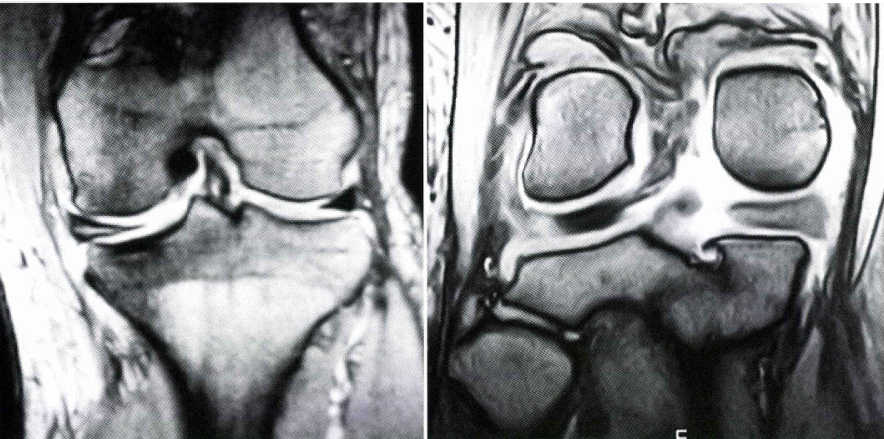

半月板とは膝の骨と骨の間のクッションであり、膝を安定化させる役割があります。その半月板が損傷することで膝の痛みが生じることを半月板損傷と言います。損傷の原因は複数あり、膝を捻るなどの大きな力が膝に加わることにより生じるもの、繰り返す微外傷により生じるもの、解剖学的破格を原因としているもの(円板状半月板、膝窩筋腱溝付近のhypermobile meniscusなど)。加齢による変性に起因するもの、などに分類できる。また靱帯損傷に合併するものでは前十字靱帯(以下、ACL)損傷が一番多く、脛骨が前方に亜脱臼するため、内・外側ともに、中-後節部の縦断裂が生じることが多いです。

膝の痛み、圧痛の場所、可動域、水が溜まっているかどうかを診察で確認します。またマックマーレーテストと言い膝をねじることで痛みを誘発する診察法も行うことがあります。レントゲンを行い、膝の関節の隙間があるかどうか、変形性があるかどうかもチェックします。半月板損傷を疑う場合はMRIを行うことで半月板損傷の確定診断を行います。